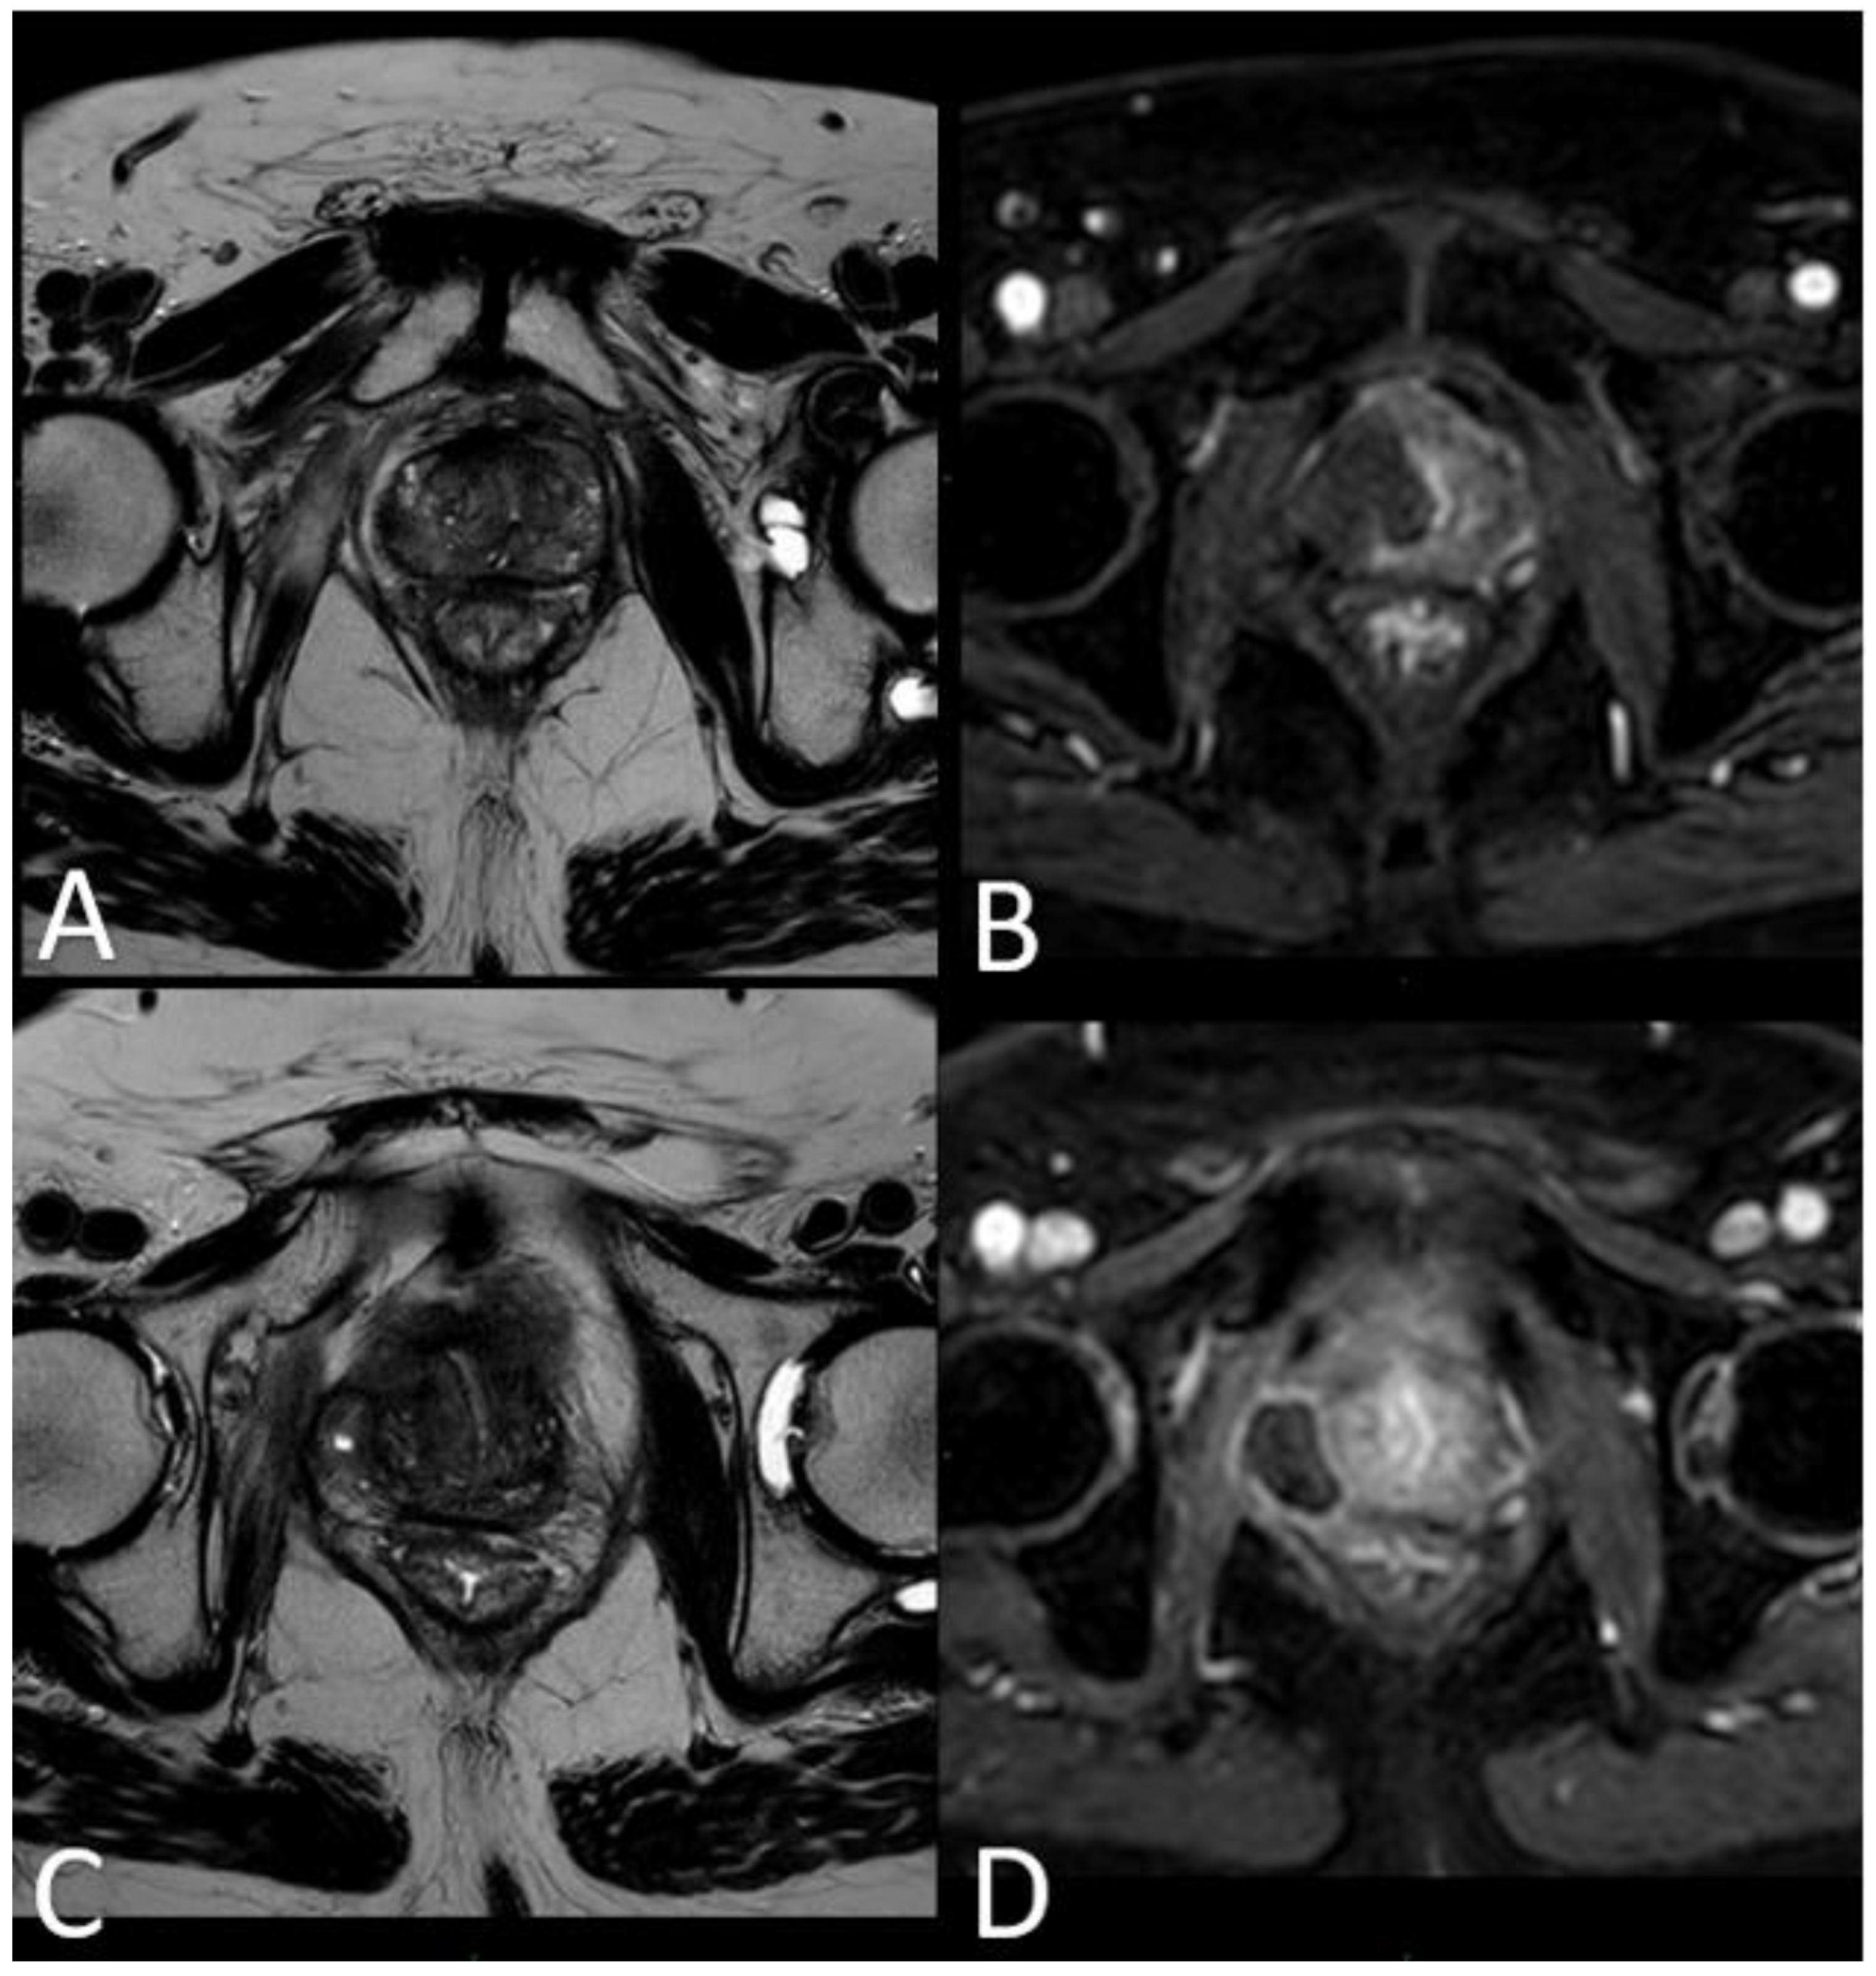

Subsequent mpMRI assessments conducted during the follow-up period portrayed the temporal evolution of this cavity, which began to exhibit a noticeable reduction in size after the 6-month follow-up, with an average volume decrease exceeding 80% by the 36-month mark (Table 4, Graphic 2).

According to the statistical analysis, the authors have observed a significant decrease also in cavity volume values that were, respectively, always between 80%-83% for all the patients at 1 year after the treatment (Table 4, Graphic 2). The percentages of cc cavity decreasing are always between 93%-95% at 2 years from the treatment. The percentage of decrease in cc cavity values is always lower than the 3% between the 2 and the 3 years. The decrease is considered significant in the first 24 months. The authors have estimated an error of 5% during the data acquisition phase.

At 1 month - 6 months - 12 months: the main findings included the laser fiber tracks surrounded by a large elliptical-shaped necrotic tissue cavitation, which appeared hypointense on T2-weighted images (Figure 2 c, d; Figure 3).

At 24 months - 36 months: presence of a T2W hypointense scar tissue that almost completely replaced the original cavity (Figure 4).

Figure 3. (a) T2-w sequence on axial plane: coagulation necrosis area (hypointense in T2W imaging) is smaller because of necrotic tissue reabsorption. (b) DCE T1-w Dixon sequence: non enhancing devascularized area (hypointense in T1W+C imaging) is smaller in size compared with the 1st month MR-follow up.

Figure 4. (a) T2-w axial sequence: small cavity filled with fluid. Some fibrotic tissue on the posterior edge of the right gland, with an external capsule retraction. Band like right-side recto-prostatic angle hypointensity on T2-w imaging is the effect of mesorectum liponecrosis. (b) DCE T1-w Dixon sequence with fat suppression on axial plane: millimetric unenhancing cavity resembling a small cavity filled with proteinaceous fluid. Necrotic tissue is reabsorbed. Capsule retraction is visible.